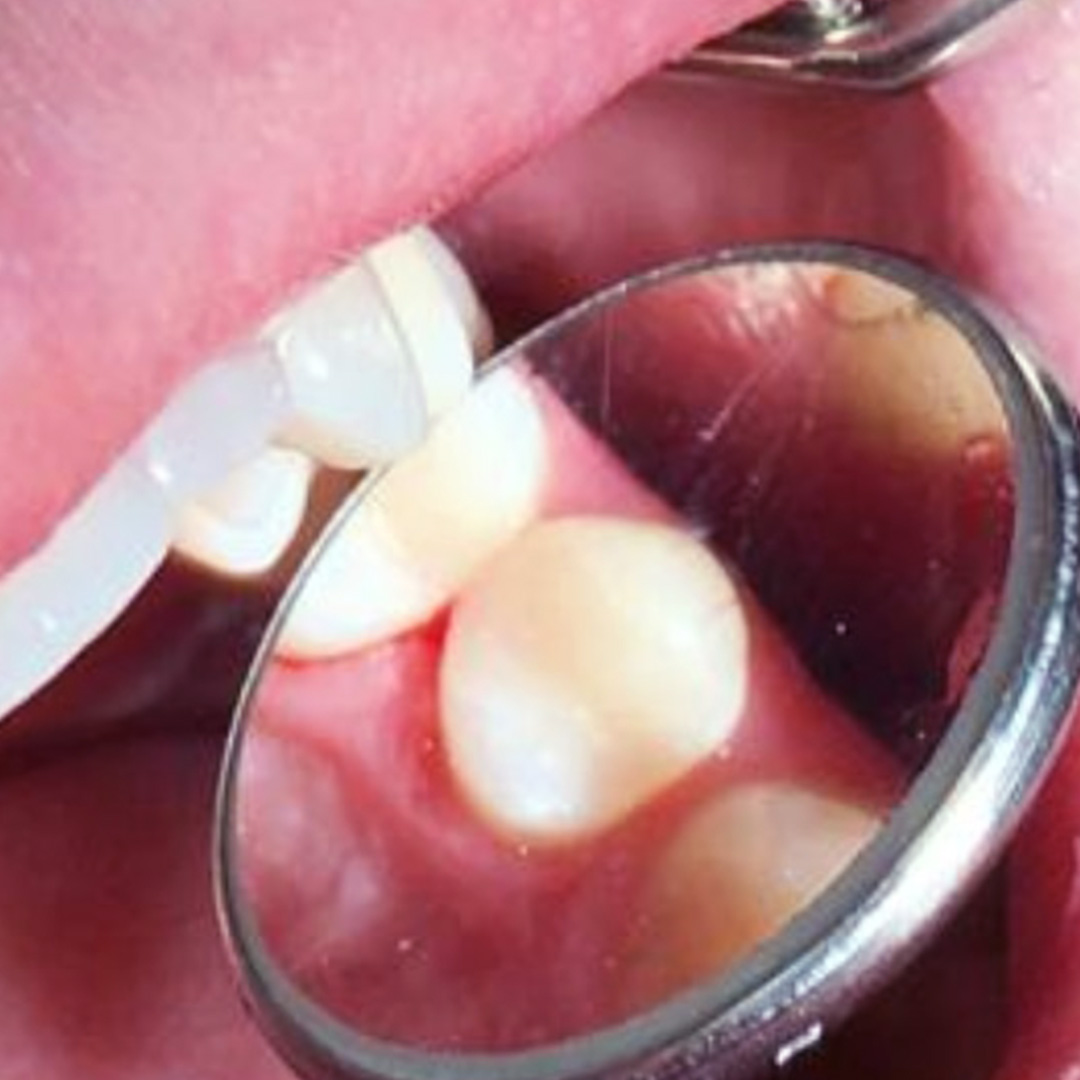

К нам обратился пациент с жалобами на боль в области 24 зуба. Неприятные ощущения беспокоили его во время приёма пищи и при контакте с холодным. Боль носила быстро проходящий характер. Похилько Надежда Геннадьевна провела осмотр и поставила диагноз: глубокий кариес 24 зуба.

В процессе лечения были проведены работы:

- механическая обработка кариозной полости с использованием системы коффердам;

- пломбирование с применением композита светового отверждения Estelite;

- проведено микроконтурирование и макроконтурирование пломбы.